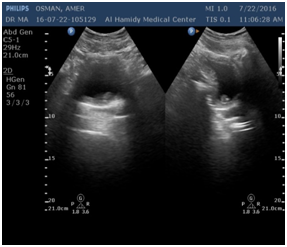

The first and most clinical and cost effective diagnostic tool are urine analysis and ultrasound (Figure 5). CT scan might be used later for further evaluation (Figure 5).

Figure 5 Urothelial cancer in different modalities.